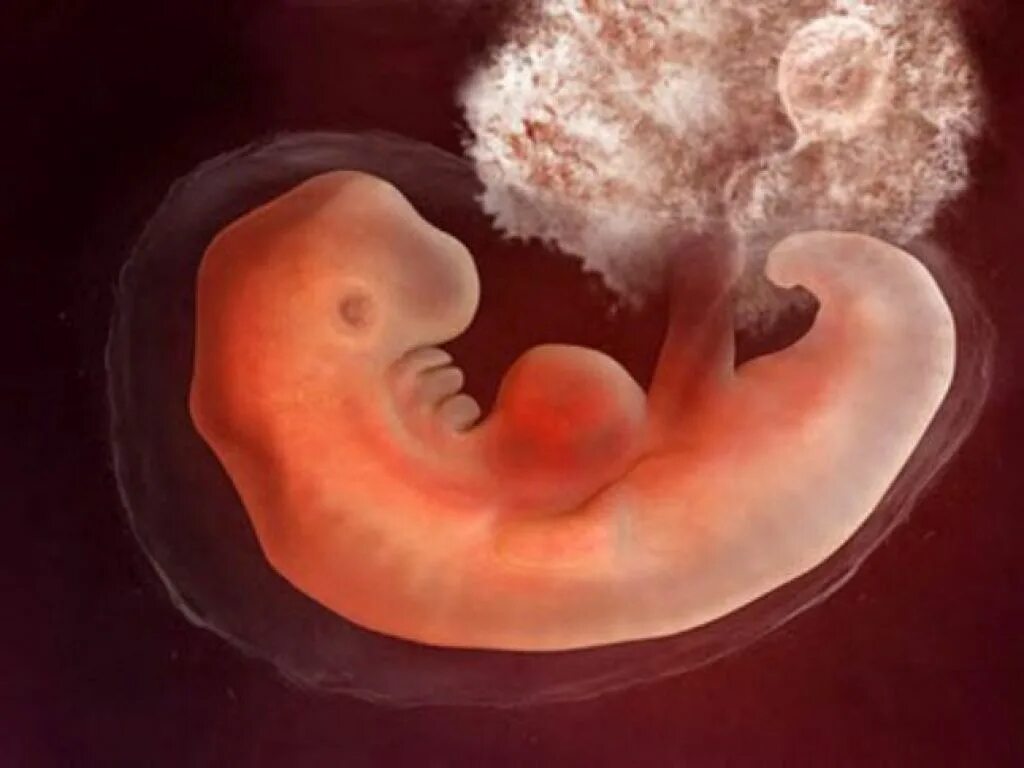

Куда девается эмбрион